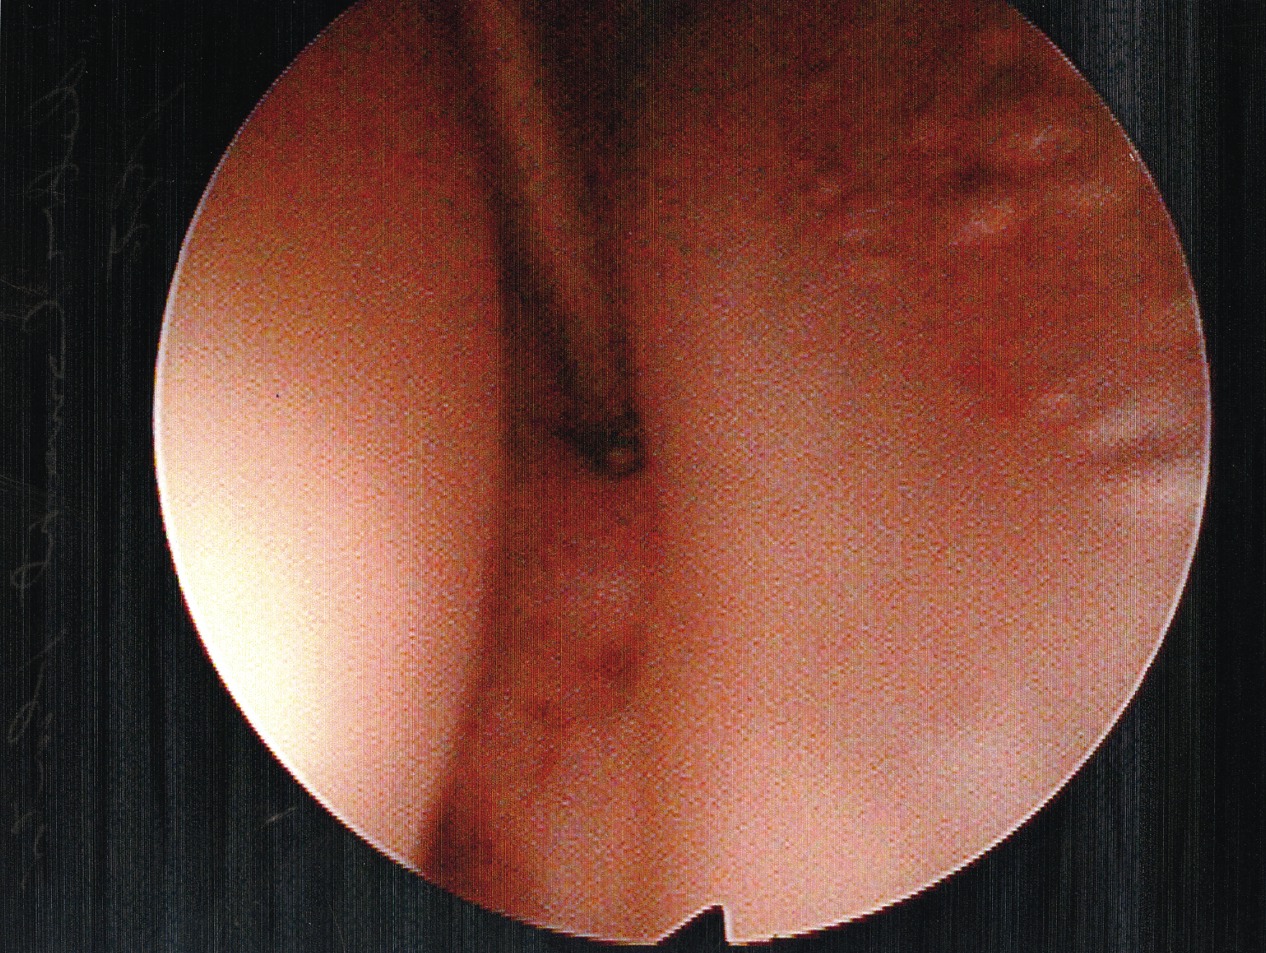

Accordingly, we recently undertook a study to evaluate the technical ease of using this approach to treat patients with plantar plate derangement, metatarsalgia and synovitis of the second metatarsophalangeal joint complex, and to assess early postoperative clinical findings. In regard to the surgical repair, we initially address the metatarsalgia, proceed to repair the plantar plate derangement and finally, using the radiofrequency-based device to ablate the synovitis affected tissue of the second metatarsophalangeal joint complex, we perform the microcapsulotomies of the plantar plate. To treat the plantar plate derangement, one makes an s-shaped incision from the distal third of the second metatarsal shaft and carries the incision to the base of the proximal phalanx. Then you would expose the superior aspect of the head and neck of the metatarsal via sharp dissection. Proceed to open and expose the dorsal aspect of the metatarsophalangeal joint. Then we perform a shortening Weil-type osteotomy of the second metatarsal.9,10 We perform the osteotomy from the dorsal distal aspect of the metatarsal and translate it toward the proximal plantar, just proximal to the plantar condyles and parallel to the plantar aspect of the foot. We adjusted the distal osteotomized capital fragment proximally (3 to 5 mm) to eliminate clinical prominence of the metatarsal head in the plantar position. We proceeded to fixate the osteotomy site with two 0.035 mm guide wires and secured it with either a 2.0 mm or a 2.4 mm compression screw. After decompression of the second metatarsophalangeal joint and internal fixation of the second metatarsal shaft, we applied gentle digital traction to distract and open up the second metatarsophalangeal joint complex. Using a 2.7 mm angled arthroscope, one can evaluate the joint to determine the extent of the synovitis. Following inspection, the surgeon can perform a synovectomy using the Topaz microdebrider device (ArthroCare) as directed by the manufacturer’s instructions. With continued digital traction, we examined the plantar capsular structures and plantar plate. We used the Topaz device to perform the microcapsulotomy procedure in the degenerated plantar plate. The purpose of this step is creating a low-grade inflammatory response necessary for stimulating a healing response in the degenerated tissue. For both ablation procedures, one can use the Topaz device at controller setting 4. For the microcapsulotomy, however, we used the system timer (set at 0.5 seconds) while making each microablation in order to specify a sufficient ablation. We created microablations over the affected tissue region to form a grid-like pattern. Every fourth microablation was slightly deeper in order to ensure adequate penetration of treatment. The affected plantar plate area usually required nine to 12 microablations. After concluding the microablation portion of the procedure, we irrigated the treated area and closed it in standard fashion. We subsequently repaired any associated contributory deformities, such as hallux adductovalgus and/or hammertoe deformity as appropriate. In regard to the radiofrequency-based portion of the procedure, it was slightly more challenging than surgical resection. However, it did offer the benefit of preserving the plantar plate and avoided a plantar incision.